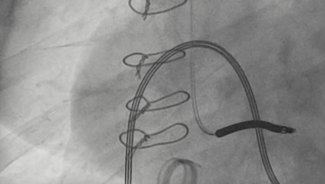

04/16/2026

Arber Kodra, MD; Danyal Khan, MD; Michael Kim, MD; Tak Kwan, MD

A 69-year-old man was referred for percutaneous coronary intervention of a right coronary artery in-stent complete total occlusion, which had collateral supply from the left anterior descending artery.